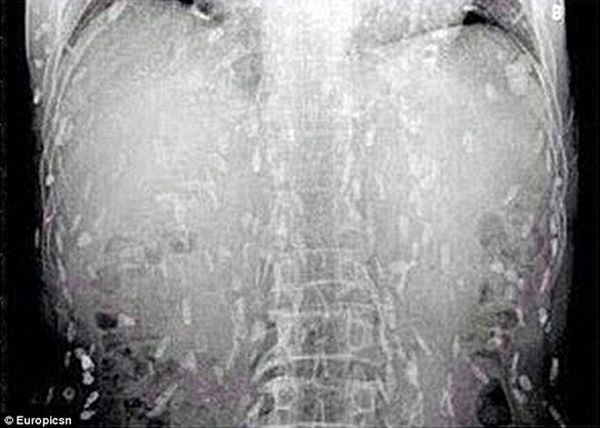

Hay như trường hợp của một người Trung Quốc bị nhiễm sán dây khắp cơ thể do ăn quá nhiều sushi là một minh chứng khác cho việc ăn đồ sống hoặc đồ nấu chưa chín có thể khiến cơ thể nhiễm nhiều loại giun, sán. Cơ thể anh “thủng lỗ chỗ” với đầy sán dây (sán xơ mít).

Trước đó, người này đã đến bác sĩ khám và than phiền về việc đau bụng, ngứa da. Kết quả quét toàn bộ cơ thể cho thấy sán dây ký sinh trên khắp cơ thể của bệnh nhân. Người này cho biết trong thời gian dài, anh là tín đồ của món sashimi (cá sống). Do đó, các bác sĩ tin rằng nguyên nhân người đàn ông nhiễm sán là do ăn quá nhiều cá và thịt chưa nấu chín kiểu Nhật.

Tình yêu shushi của một người Trung Quốc gần như đã tắt lụi sau khi món ăn này khiến cơ thể anh nhiễm đầy sán.